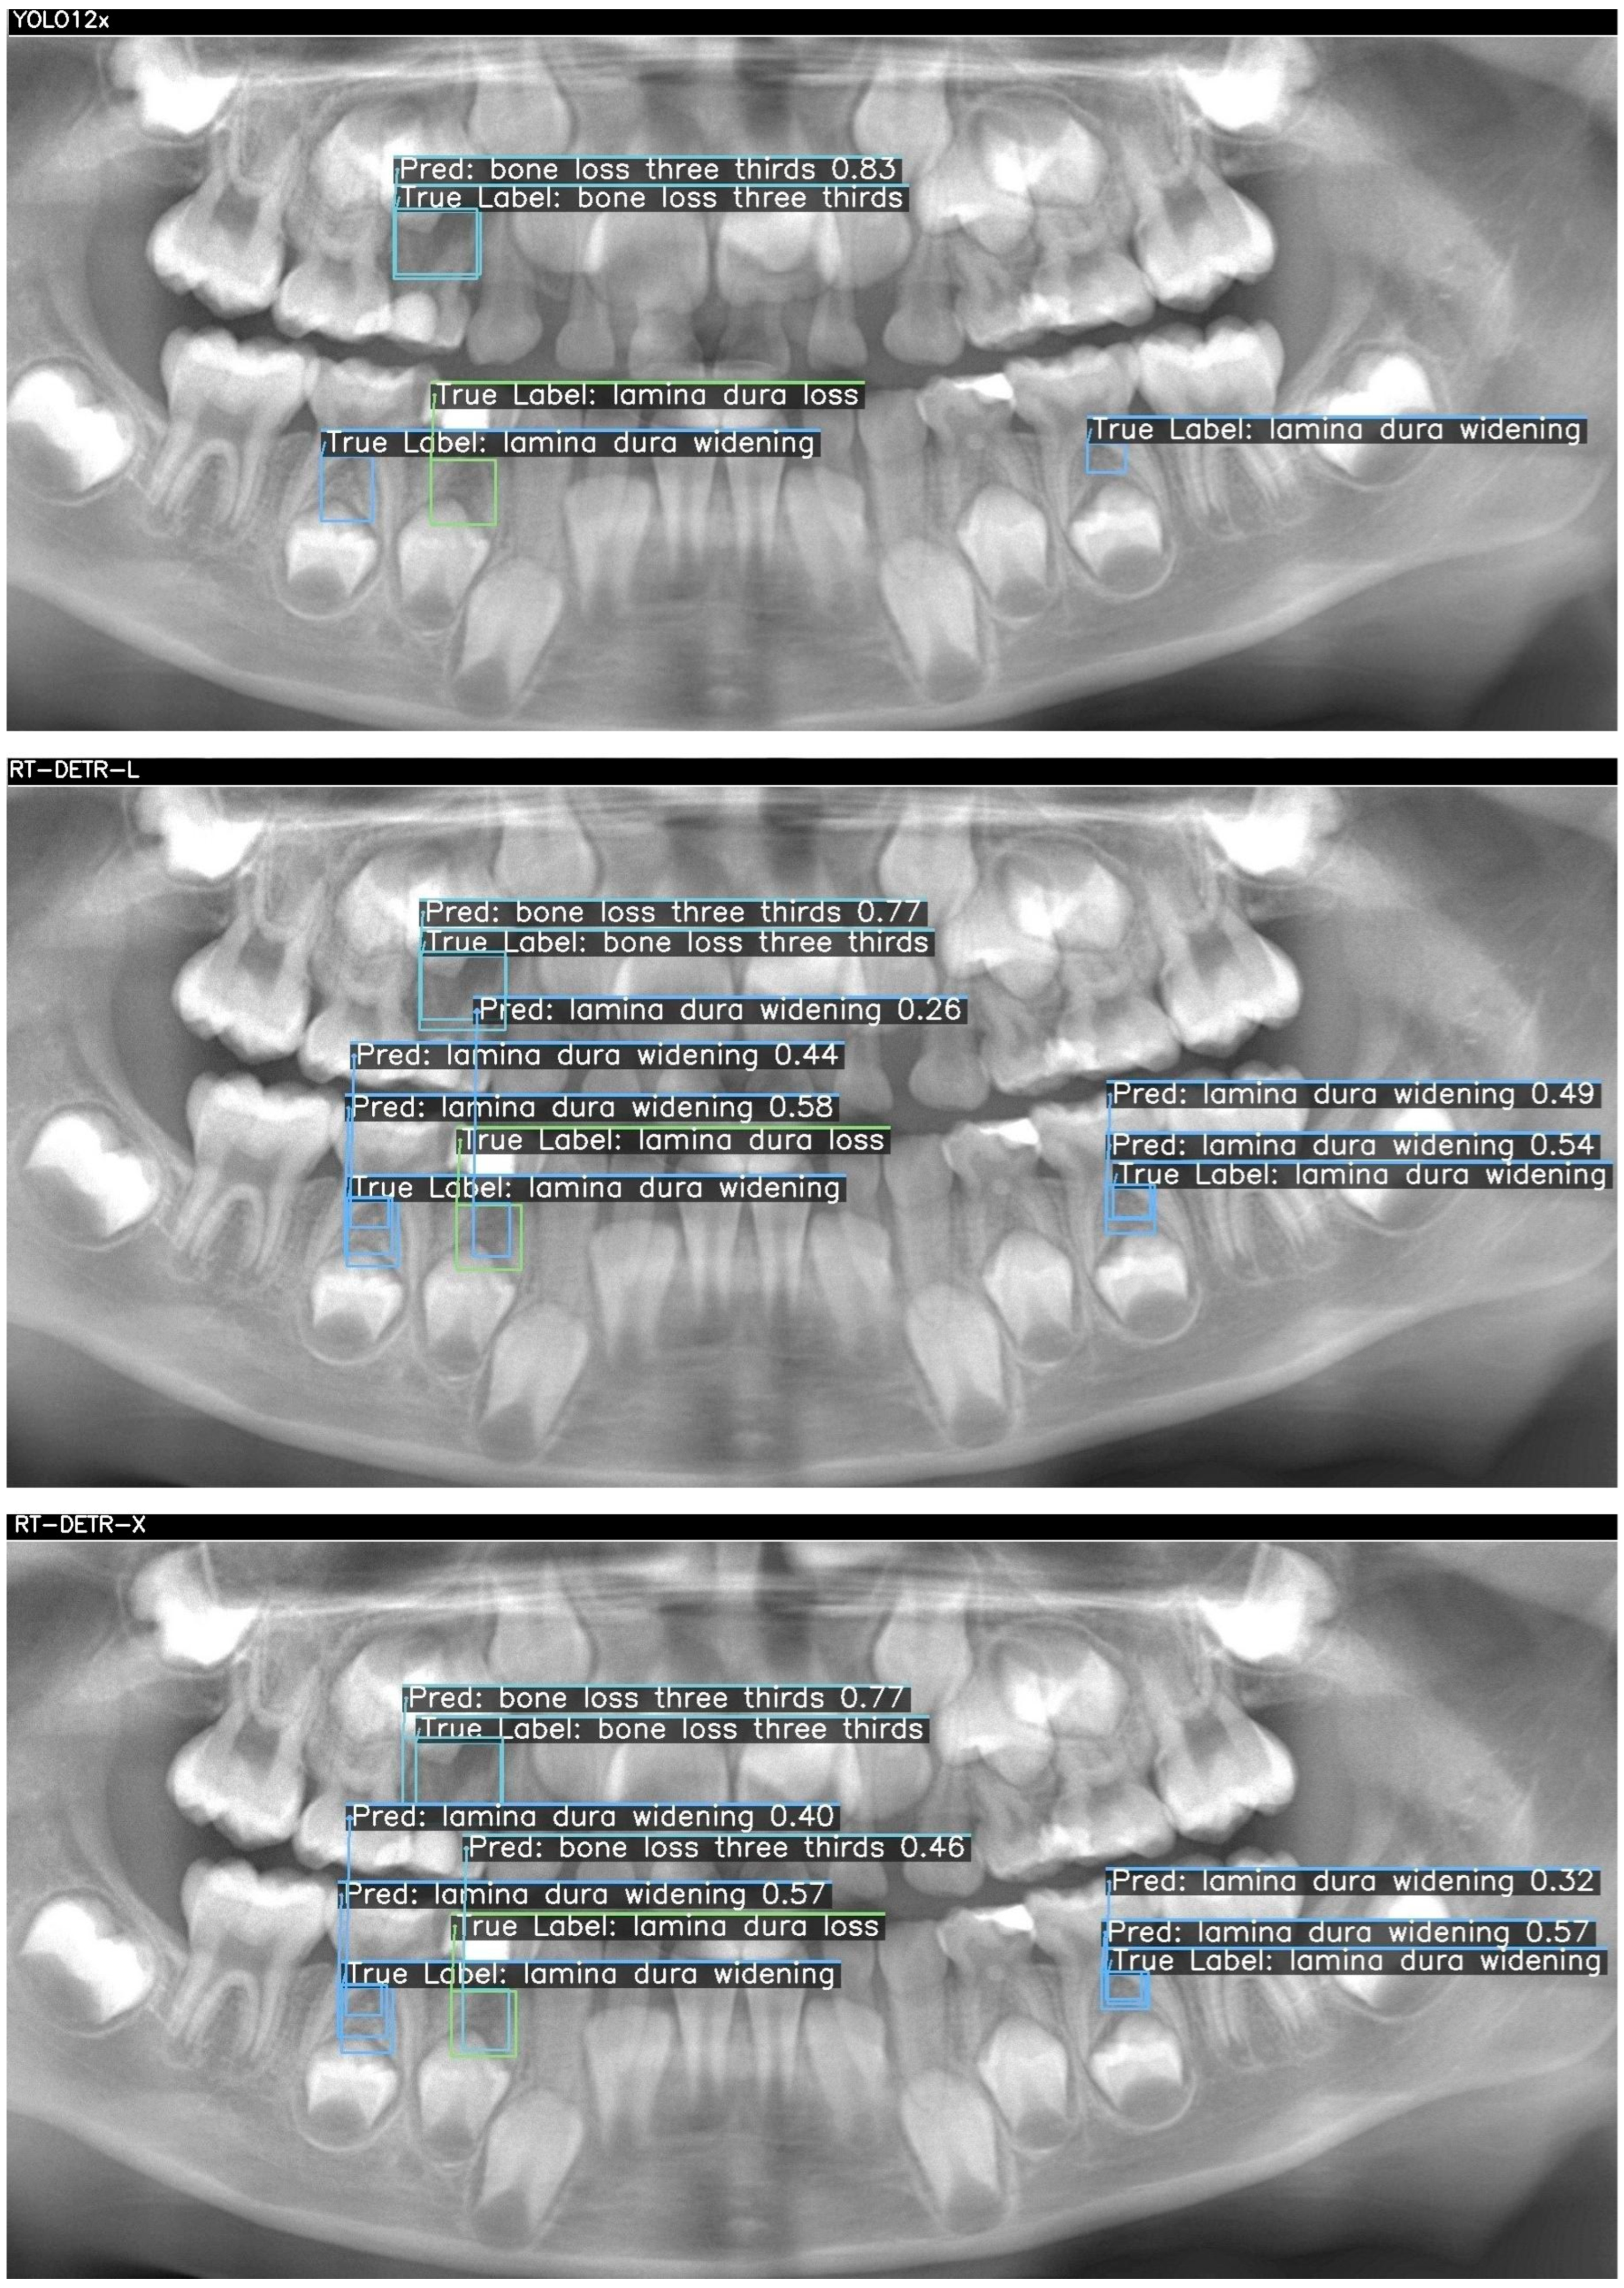

Below, two sample cases are presented as Figure 2 and Figure 3. For each case, outputs from YOLOv12x (top), RT-DETR-L (middle), and RT-DETR-X (bottom) were displayed. The "True Labels" annotated by the expert and the prediction (Pred) boxes marked by the model were color-coded in green, blue, and orange to differentiate the diseased regions during visualization.. Figure 2 and Figure 3 visualize these differences, showing that YOLOv12x frequently misses subtle lamina dura changes, RT-DETR-L captures more lesions but at the expense of false positives, while RT-DETR-X maintains superior balance by detecting both conspicuous and subtle lesions with minimal error. These visualizations further confirm the trends seen in Table 7.

In Figure 2, three ground-truth lesions were annotated on the panoramic radiograph: a central “bone loss three thirds” and two “lamina dura widening” regions in the lower molar areas. The YOLO12x model correctly detected only the central bone loss lesion (confidence = 0.83), but failed to identify either lamina dura widening (TP = 1, FN = 2, FP = 0). RT-DETR-L improved recall by capturing the bone loss (0.77) and one widening (0.44), yet introduced a spurious “lamina dura loss” prediction (TP = 2, FN = 1, FP = 1) and exhibited modest confidence scores (0.26–0.58). In contrast, RT-DETR-X achieved perfect coverage—detecting the bone loss (0.77) and both widenings (0.57, 0.32) without any false positives or negatives (TP = 3, FN = 0, FP = 0)—demonstrating superior balance between precision and recall in this challenging case as summarized in Table 7.